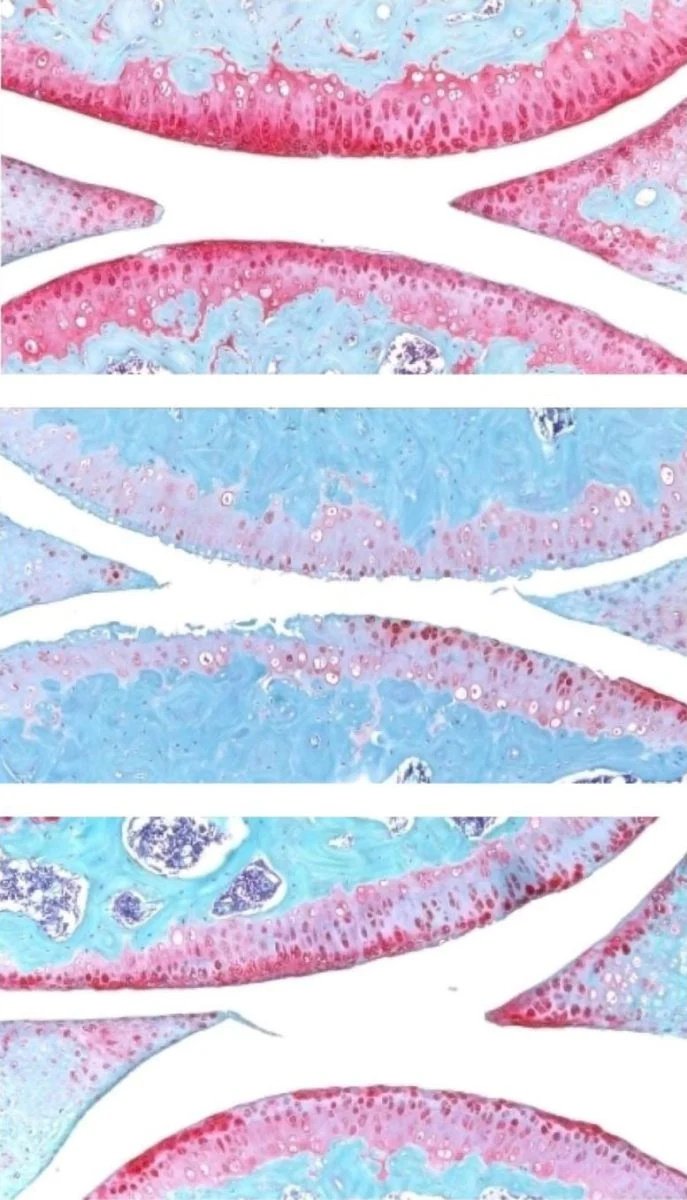

(图2)

上图:年轻小鼠的膝关节;中图:老龄小鼠的膝关节;下图:经过治疗的老龄小鼠膝关节。红色部分表示软骨。图片来源:Nidhi Bhutani

随后,他们尝试给老龄动物注射一种能抑制 15-PGDH 活性的小分子药物——首先是腹部注射(影响全身),然后是直接注射到关节中。在这两种情况下,老龄小鼠原本明显变薄、功能退化的膝盖软骨,都在关节表面重新变厚了。进一步的实验证实,关节中的软骨细胞生成的是高质量的透明软骨,而不是功能较差的纤维软骨。

1. “坏分子”减少:一种表达 15-PGDH 并参与软骨降解的细胞,治疗后比例从 8% 降至 3%。

2. “疤痕制造者”减少:另一种不表达 15-PGDH 但表达纤维软骨(类似疤痕组织)生成基因的细胞,治疗后比例从 16% 降至 8%。

3. “再生主力”增加:第三种细胞群不产生 15-PGDH,但表达形成透明软骨和维持细胞外基质所需的基因,治疗后其比例从 22% 飙升至 42%。

这些发现表明,治疗后基因表达发生了整体转变,恢复到了更年轻的软骨构成——而且这一过程完全没有干细胞或祖细胞的参与。